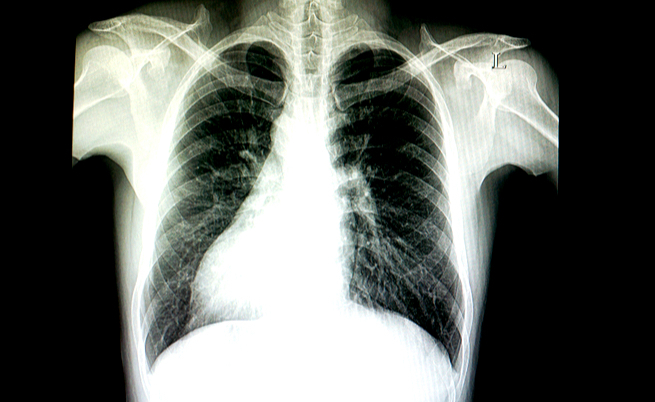

situs inversus: cos'è

C’è chi nasce con gli organi invertiti. Lo sapevate?

Il Situs Inversus colpisce circa 1 individuo su 10.000: chi ne è affetto, presenta gli Organi Interni Invertiti. Leggi qui!